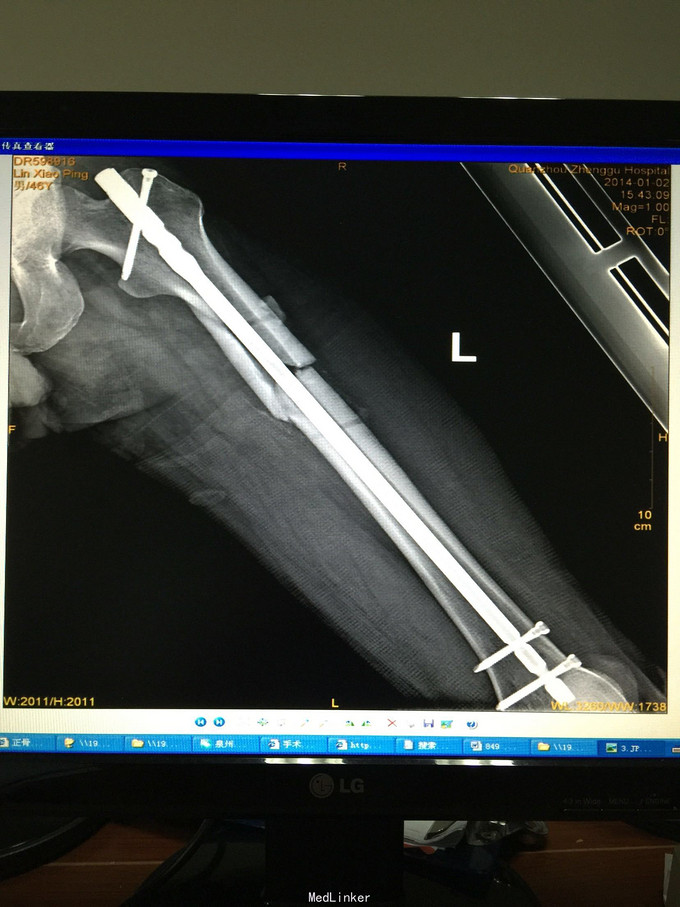

左股骨中上段骨折术后骨不连

主诉:左股骨骨折术后伴局部酸痛11个月

诊断:左股骨中上段骨折术后骨不连 处理:左股骨骨折术后骨不连断端清理+防旋钢板内固定+取髂骨植骨术

术后半年 讨论 考虑股骨中上段骨折 应力集中 近段一枚螺钉稳定性不够?